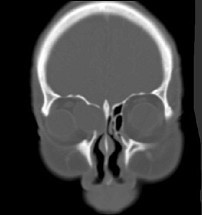

患者,女性70岁,因双眼视力骤降半天就诊。检查:右眼视力0.02,左眼0.03,结膜无充血,角膜透明,角膜后沉着物阴性,瞳孔对光反射对称、迟钝,晶状体轻度混浊,玻璃体无混浊;视乳头充血水肿。(如图)请问首选需行哪种检查()

-

患者,女性70岁,因双眼视力骤降半天就诊。检查:右眼视力0.02,左眼0.03,结膜无充血,角膜透明,角膜后沉着物阴性,瞳孔对光反射对称、迟钝,晶状体轻度混浊,玻璃体无混浊;视乳头充血水肿。

如VEP为各波潜伏期延长、波幅下降;眼底荧光造影为视盘高荧光;视野为巨大中心暗点;CT无异常;视力下降经验光试镜无法矫正。则诊断为()

- 患者,女性70岁,因双眼视力骤降半天就诊。检查:右眼视力0.02,左眼0.03,结膜无充血,角膜透明,角膜后沉着物阴性,瞳孔对光反射对称、迟钝,晶状体轻度混浊,玻璃体无混浊;视乳头充血水肿。下列有关本病的治疗原则中错误的为()